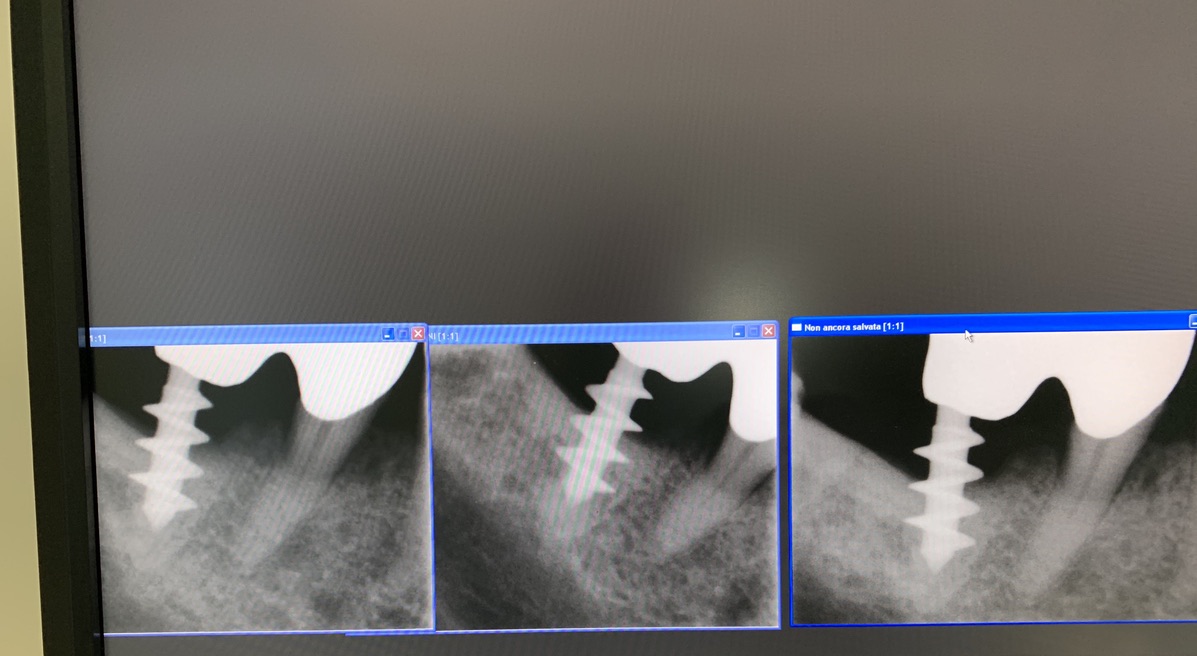

Original form of the Tramonte implant. 5 mm diameter with 3 threads. Stem diam. 2.1 mm. Neck diam. 2 mm x 5 mm in length. Grade 2 titanium. Grade 2 allowed the need to bend the implant neck to improve parallelism. It is an immediate post-extraction implant. Therefore, in the same session, extraction, boring, tapping and implant insertion. Immediately followed by monconization and the preparation of temporary crowns in light occlusion. The radiographs provided show the situation since 2010. The emergence of the thin neck favors the formation of a dense gingiva sleeve that protects against peri implantitis. The wide threads radiate the occlusal load away from the implant body, favoring the formation of a more homogeneous bone.